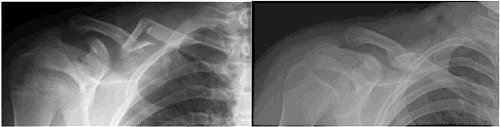

We now know that we can be similarly effective placing the arm on the side of the fracture in a sling, instead. This is the most common method of management for middle third fractures that are reasonably well aligned. When the ends heal together, they do so by laying down additional calcium in a supportive framework that you can feel with your fingers as a lump and see on an x-ray as a bonelike mass called a callus. Yes, it is just about as strong as your bone before the break. The average time between fracture and healing to allow you to safely resume riding is six weeks. If you are thin, you may be able to see that the healed side looks a little different from the uninjured one. Since most of us are not runway models, the cosmetic abnormality is a curiosity, but not something to fix.